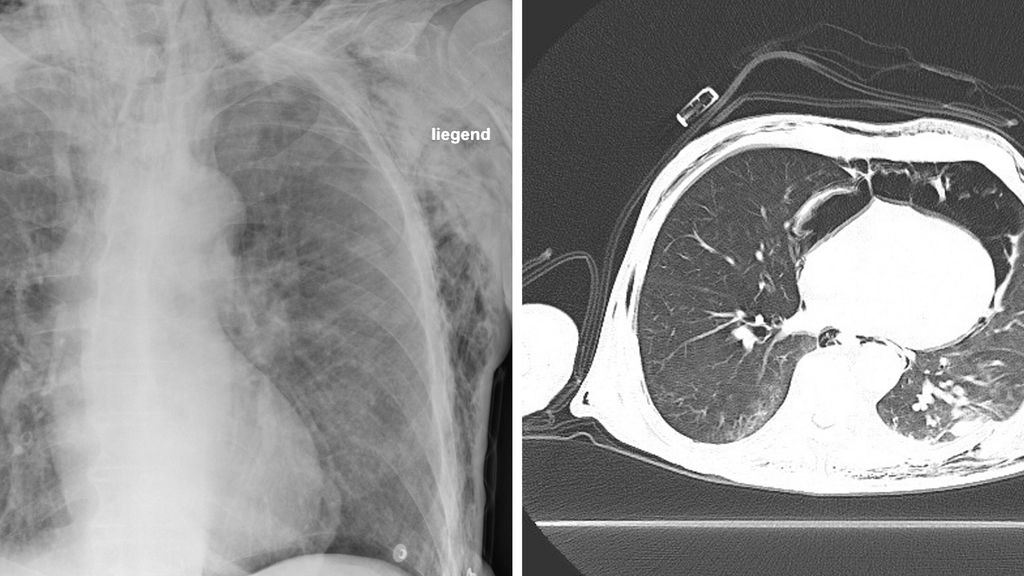

Abb. 2: Lungenröntgen eines 89-jährigen Patienten nach einem Sturz von der Leiter mit begleitendem Schädel-Hirn-Trauma und mehreren Extremitätenverletzungen. Es zeigt sich ein ausgedehntes Weichteilemphysem, Rippenfrakturen sind erkennbar, ein Pneumothorax kann nicht ausgeschlossen werden (A). Das CT zeigt das Bild eines Pneumomediastinums bei Trachealruptur sowie eine dislozierte Rippenfraktur mit lokaler Lungenparenchymeinblutung nach stumpfem Thoraxtrauma (B)